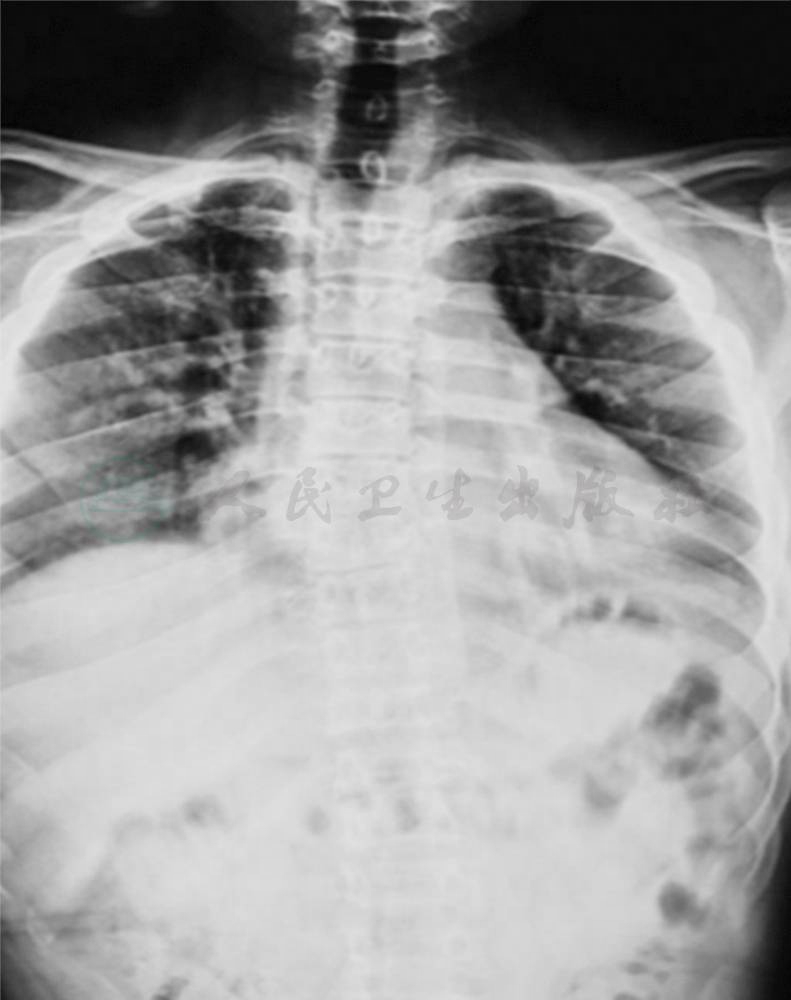

5.胸片,脊柱正位片(图2)平T2~T4椎体水平气管稍向右侧移位。以T7为中心脊柱轻度向左侧弯,多发椎体高度变扁。

图2 胸片,脊柱正位片